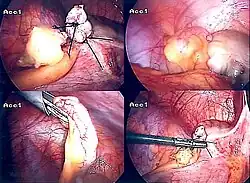

Grundsätzlich bleibt die Operation indiziert, wenn eine akute Appendizitis, die eine bedrohliche Bauchfellentzündung (Peritonitis) verursachen kann,[20] nicht mit hinreichender Sicherheit auszuschließen ist. Das Risiko der negativen Appendektomien ist geringer anzusetzen als das Risiko der akuten Appendizitis. Bei bis zu 28 % der Patienten wird bei der Operation eine Perforation der Appendix festgestellt, die mit einer Letalität (Sterblichkeit) von ca. 10 % einhergeht (beim Auftreten einer diffusen Peritonitis bis zu 30 %).[21] Dabei sollte möglichst früh (innerhalb von etwa 48 Stunden) operiert werden. Die Appendektomie kann offen chirurgisch durch den sogenannten Unterbauchwechselschnitt (sog. Laparatomie) durchgeführt werden oder laparoskopisch mit Hilfe einer in die Bauchhöhle eingeführten Kamera und weiteren Arbeitszugängen (sog. minimalinvasive Laparoskopie bzw. „Schlüssellochchirurgie“).

Eine bei perforierter Wurmfortsatzentzündung, wie sie seit dem 18. Jahrhundert bekannt ist (1759 Mestivier, Lamotte 1766[33]), durchgeführte Entfernung der Appendix vermiformis erfolgte auch 1887 durch George Thomas Morton.[34] Einer der ersten deutschen Chirurgen, der sich für die operative Entfernung des entzündeten Wurmfortsatzes einsetzte, war der gebürtige Mecklenburger Bernhard Riedel (seit 1888 Ordinarius und Direktor der Chirurgischen Klinik in Jena). Gleichzeitig mit dem Amerikaner Charles McBurney erarbeitete Riedel den Wechselschnitt als Operationstechnik. McBurney, der ebenfalls die Frühoperation bei Appendizitis propagierte, veröffentlichte 1889 vor der New York Surgical Society seinen klassischen Bericht über das frühzeitige operative Eingreifen, welches durch John Murphy (1857–1916) populär gemacht wurde und sich ab etwa 1910 auch in Europa allgemein durchsetzte.[34][35] McBurney beschrieb die Stelle des stärksten Schmerzes im rechten Unterbauch, die seither als McBurney-Punkt bekannt ist. Nach den ersten chirurgischen Erfolgen bei der Blinddarmentzündung wurde die Krankheit für mehrere Jahrzehnte eine rein chirurgische Angelegenheit. Der Chirurg diagnostizierte und operierte sie. Das führte zu einer relativ hohen Zahl von Blinddarmoperationen. Ein Meilenstein in der chirurgischen Technik war die Einführung und Verbreitung der laparoskopischen Appendektomie in den Jahren 1980 bis 1990.